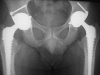

The concept of a dual articulation acetabular cup was developed by Prof. Bousquet in 1974. This concept has been shown to provide high stability after revision and primary total hip arthroplasty. The aim of our study was to evaluate the incidence of prosthetic instability in a consecutive homogeneous series of 384 primary dual mobility cups. Incidence of instability and implant survival were evaluated. Mean follow-up was 15.3 years (range, 12-20). There was no early or late instability. On the acetabular side there were 13 aseptic loosenings, 14 intraprosthetic dislocations, and seven polyethylene wear cases that required replacement of the liner. The cumulative survival rate of the dual-articulation acetabular cup using surgical revision for aseptic loosening as the endpoint was 95.9% +/- 4.1% at 18 years postoperatively. Our series proves the good long term behaviour of dual-articulation acetabular components in primary arthroplasty. Their excellent survivorship rate and the absence of episodes of prosthetic instability increase our confidence in this concept.